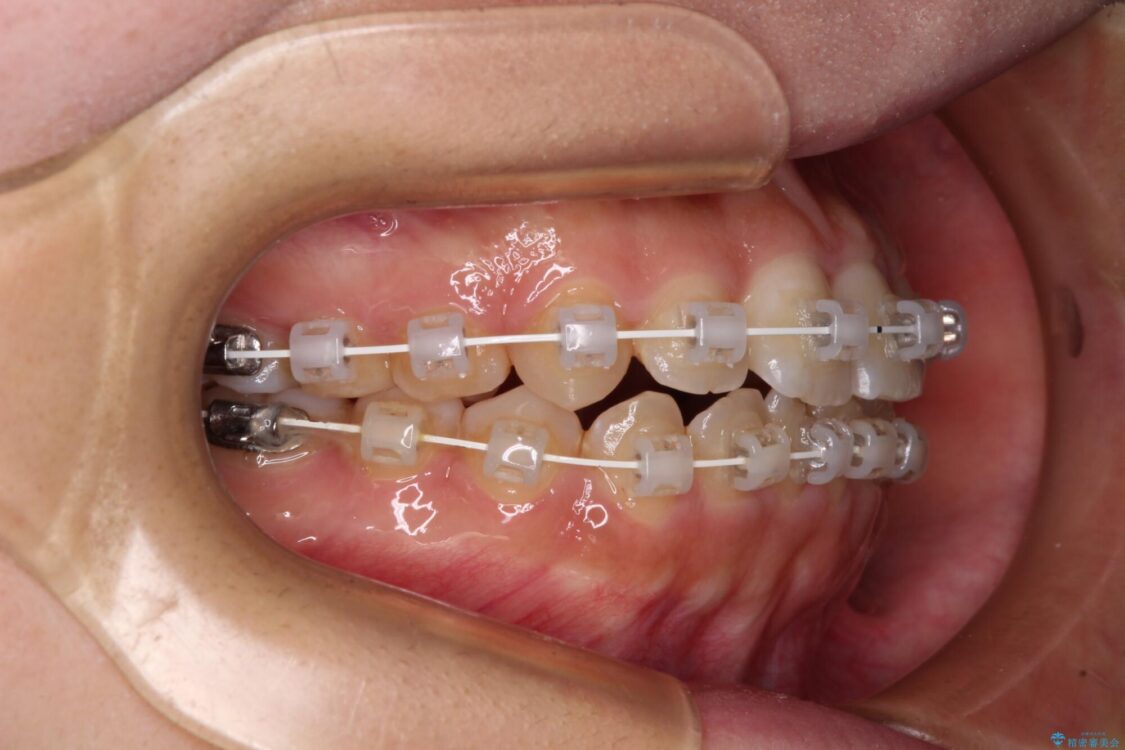

治療途中

• 【モニター】短期間で終わりたい ワイヤー装置での非抜歯矯正 治療途中画像